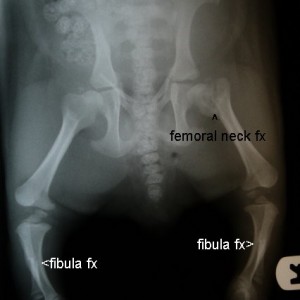

X-Ray Machine

Through borrowed funds we acquired an x-ray machine – and now have digital radiograph capabilities that speed up the diagnosing process which in turn reduces the stress on the injured wombats. Any contribution toward this much needed equipment and the ongoing supplies would be highly appreciated, here through our donations page.